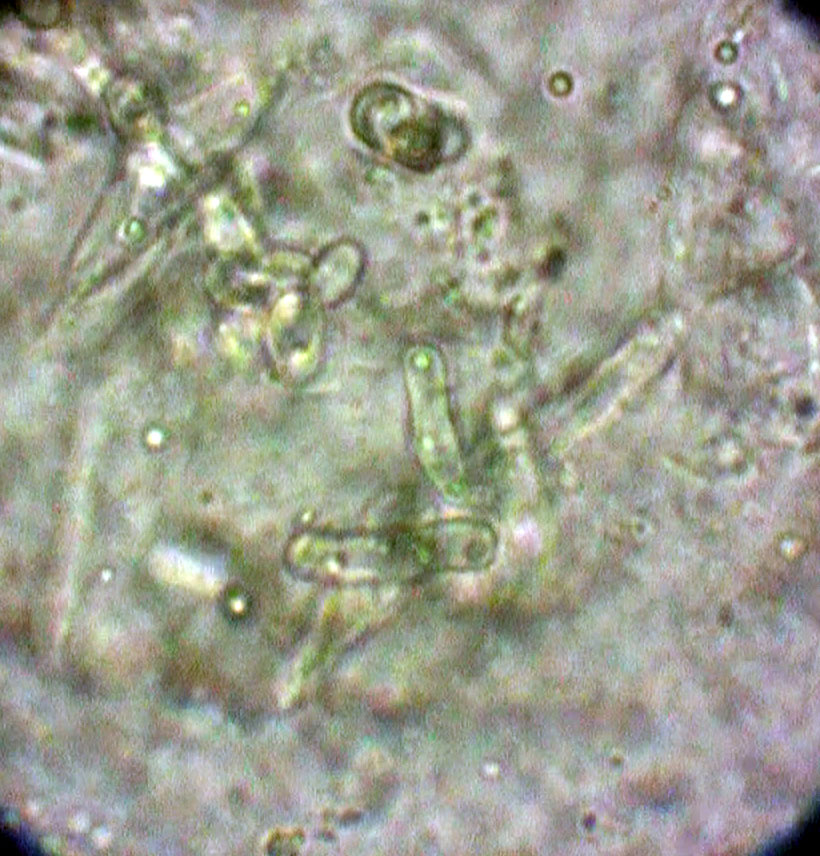

口腔内やそ嚢液を顕微鏡で観察して直接発見します。

通常細菌より10倍ほど太、菌糸が伸びている状態を確認します。